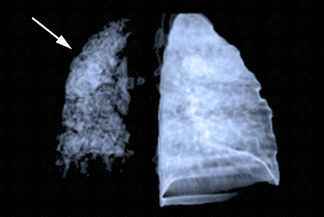

Texto alternativo para a imagem

Texto alternativo para a imagem Créditos: Dra. Elazir Mota - Rio de Janeiro/RJ

Descrição das imagens: Paciente infantil, sexo feminino, 8 anos, com história de aspiração de corpo estranho (milho de pipoca) diagnosticado tardiamente. Tomografia de tórax revela substituição de todo parênquima pulmonar esquerdo sendo ocupado por extensas bronquiectasias, de caráter sequelar. Observa-se na reconstrução tridimensional (3D) a importante destruição do parênquima pulmonar à esquerda (seta branca).